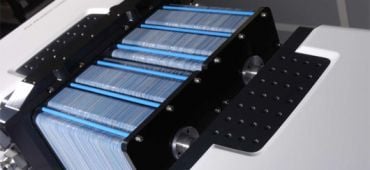

Conçue par Philippe Cinquin et Serge Cosnier, chercheurs à l’université Joseph-Fourier de Grenoble, la biopile est miniature et génère son énergie grâce au glucose et à l’oxygène présent dans le sang. L’énergie n’est pas accumulée par cette pile à combustible comme dans une pile classique mais produite directement. Des enzymes sont connectées électriquement aux électrodes de la pile afin de transformer l’énergie chimique en électricité.

Cette application pourrait permettre aux personnes équipées de stimulateurs cardiaques d’éviter les interventions dues à l’épuisement de leurs batteries : la batterie d’un pacemaker doit par exemple être généralement changée tous les 10 ans. La biopile pourrait en outre être positionnée plus près du cœur et être employée dans davantage d’insuffisances cardiaques qu'avec les piles employées jusqu'ici. Les chercheurs travaillent dans ce sens avec la société italienne Sorin, spécialisée dans ce domaine. De nombreuses autres applications sont envisageables, cette biopile pouvant alimenter tout appareil implanté dans le corps d'un humain ou d'un animal.

La pile à combustible peut également fonctionner hors d'un corps bien que cette option présente a priori un intérêt moindre. Elle pourrait par exemple alimenter à terme des ordinateurs dont la batterie pourrait être rechargée en versant de l’eau sucrée sur la biopile. Les partenariats et les tests se multiplient actuellement pour étendre encore les possibilités de cette biopile prometteuse.